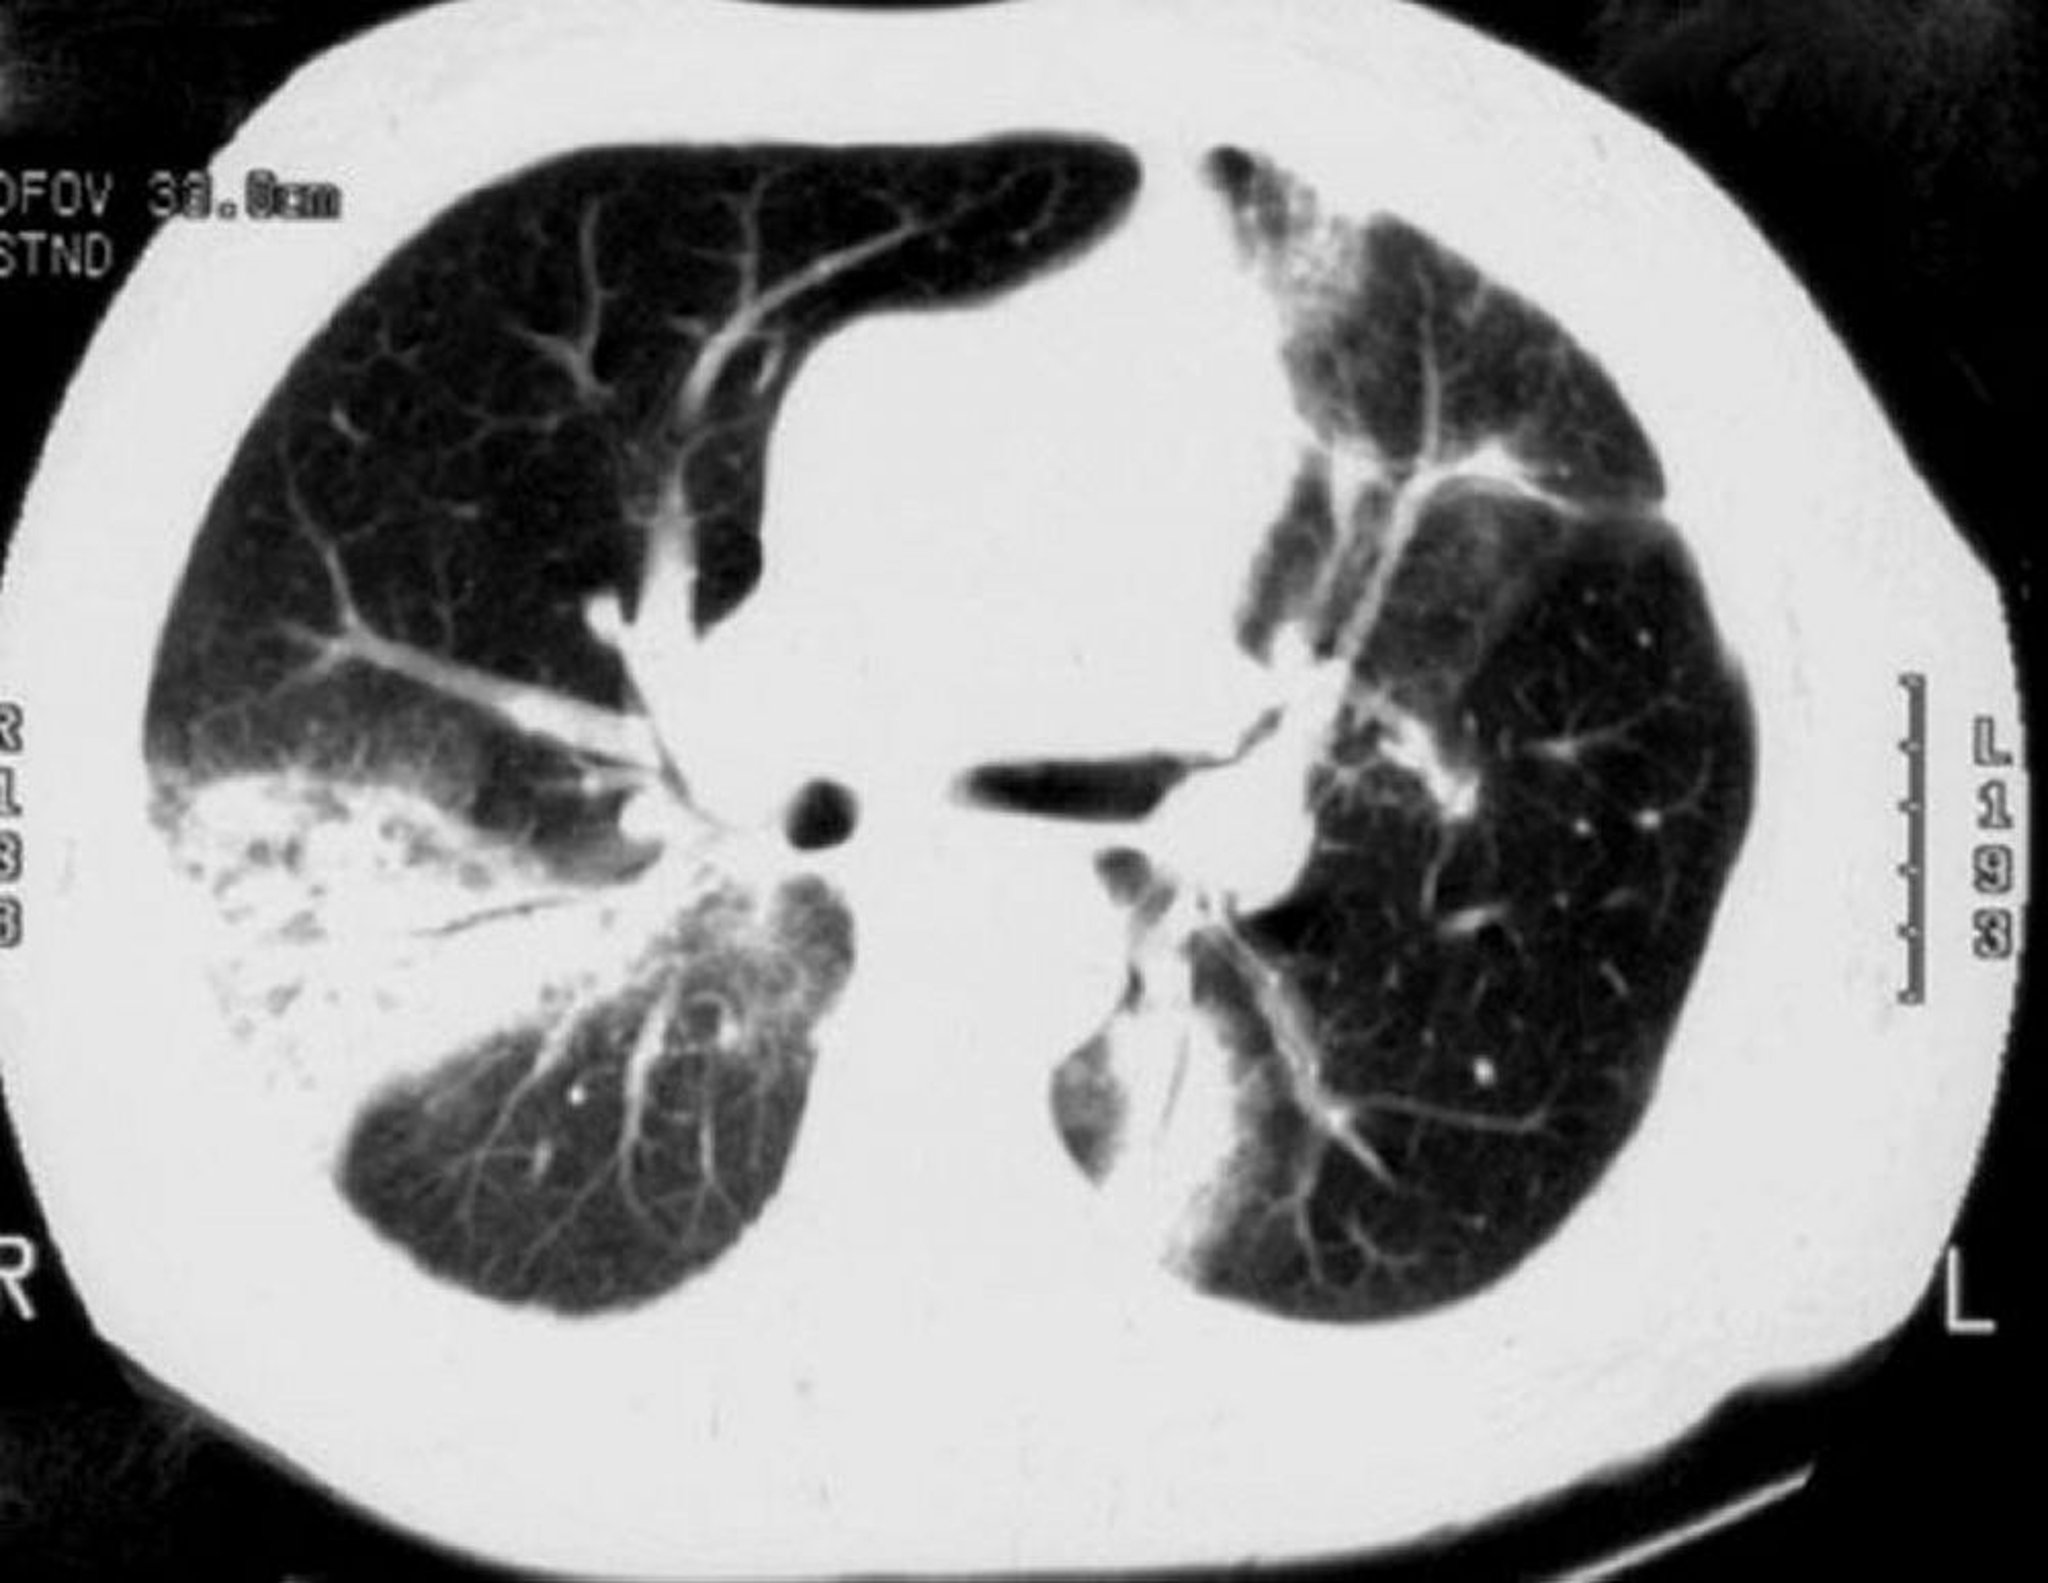

Cryptogenic Organizing Pneumonia

High-resolution CT shows patchy airspace consolidation, ground-glass opacities, small nodular opacities, and bronchial wall thickening and dilation (air bronchograms).

Image courtesy of Talmadge E. King, MD.